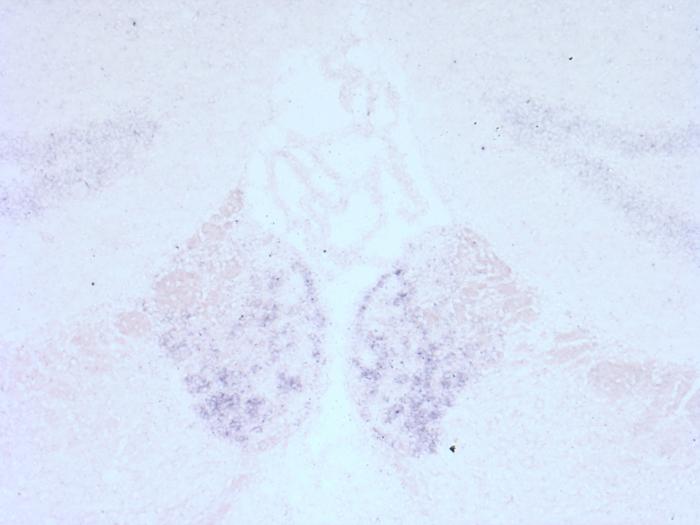

Accordingly, the team tested mice that had a mutation in this particular BK α subunit residue. First, they found that the mutation prevented alcohol from altering the firing properties of neurons in the medial habenula, a brain region with high levels of BK channels, thereby demonstrating that it also confers resistance to ethanol in mouse brain cells, not just in frog eggs. At the behavioral level, the mice harboring the mutation did not display any anomalies when compared to control littermates. Notably, they exhibited the standard signs of intoxication upon alcohol injection, such as loss of balance and hypothermia, and they consumed the same amount of alcohol when tested under various conditions of moderate or excessive drinking.